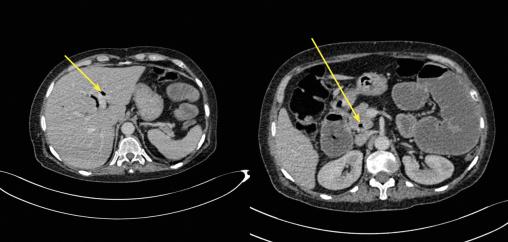

- une distension hydro-aérique de l’ensemble des anses grêliques en amont d’une formation arrondie bien limitée de densité calcique estimée à 700 UH, rappelant un calcul biliaire siégeant au niveau de l’avant-dernière anse iléale contrastant avec un aspect plat du reste du segment iléal et du côlon (fig. 1) ;